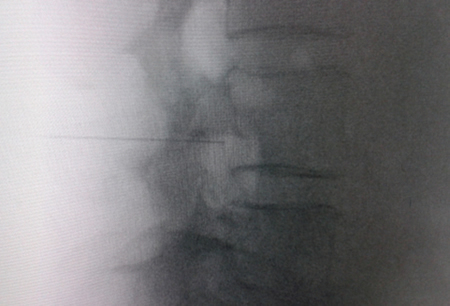

El acceso por vía transforaminal es el más utilizado (4). Se coloca al paciente en decúbito prono con una almohada a nivel abdominal para revertir la lordosis fisiológica. Las agujas o cánulas de radiofrecuencia que utilizamos con más frecuencia son de diámetro 20 o 22 G de 98 mm de largo con punta activa de 0,5 o 1 cm. Después de la asepsia con clorhexidina alcohólica y la colocación de campos estériles, se realizan enfoques radiológicos en incidencia anteroposterior, oblicuo y lateral. En incidencia anteroposterior y moviendo el arco en dirección cráneo caudal se borra el doble arco del borde inferior vertebral. En incidencia oblicua entre 20 y 30 grados ipsilateral al GRD a tratar, se visualizará la clásica imagen descrita como de “Scotty Dog”, que es resultado de acercar el macizo facetario y la apófisis espinosa al lado contralateral. El punto de entrada será entonces inmediatamente debajo del pedículo. Previa anestesia local con lidocaína al 1 %, la aguja se introducirá siguiendo una visión túnel y no se avanzará más allá de la mitad del pedículo en esta proyección con la finalidad de prevenir la lesión neural. En proyección lateral, se introducirá en el techo del neuroforamen

Fig. 1. Vista radiológica de perfil que muestra una cánula de radiofrecuencia en el ángulo anterosuperior o techo del neuroforamen, topografía aproximada del ganglio de la raíz dorsal